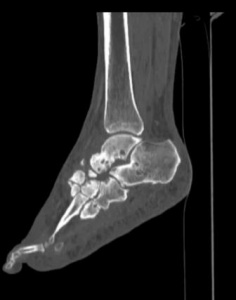

Инструментальные методы диагностики хронического остеомиелита и диабетической нейро-остеоартропатии (стопы Шарко). При ДНОАП рентгенологические признаки в англоязычной литературе описаны как симптомы пяти «Д»: joint distension (растяжение сустава), dislocation (вывих), debris (отломки), disorganization (разрушение с потерей функции), increased density (увеличение плотности) [20, 21]. Рентгенологический метод дает положительные результаты на более поздних стадиях заболевания, при потере костного вещества более 20-40 % и является малоэффективным на ранних стадиях развития ДНОАП [22, 23].

Наиболее информативным методом исследования для диагностики ДНОАП, а также для оценки степени поражения как костей, так и мягких тканей, диф-ференцировки остеомиелита от диабетической нейро-остеоартропатии и для планирования хирургического вмешательства является магнитно-резонансная томография [24, 25]. Разработаны и предложены новые методы анализа данных магнитно-резонансной томографии для оценки стопы Шарко [26, 27].

Диабетическая нейроостеоартропатия (стопа Шар-ко) - потенциально опасное осложнение для пациентов с сахарным диабетом, приводящее к значительному разрушению костей, суставов, деформации стопы и образованию трофических язв [5, 6]. С учётом высокого процента ампутаций нижних конечностей и постампутационной летальности больных сахарным диабетом (28-50 %) ранняя диагностика ДНОАП имеет важное значение [15-18]. Основным методом оценки состояния костей и суставов остается рентгенография, позволяющая с высокой достоверностью определять очаги остеолиза, но малоэффективная на ранних стадиях развития ДНОАП [22, 23]. Совершенствуются денситометрические методики исследования. Наиболее информативными методами для оценки локализации и размера очага поражения, как костей, так и мягких тканей, являются магнитно-резонансная томография [24, 25] и гистологический метод [30, 31].